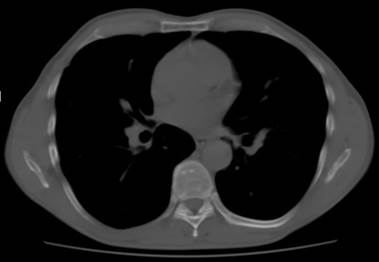

El paciente evolucionó de manera favorable y fue dado de alta. La TC de control post cirugía informa: cambios secundarios a cirugía en la región lateral y craneal del lóbulo medio, se observó tractos fibrosos de aspecto cicatricial, no se identificó masas ni nódulos en el momento actual (Figura 3).